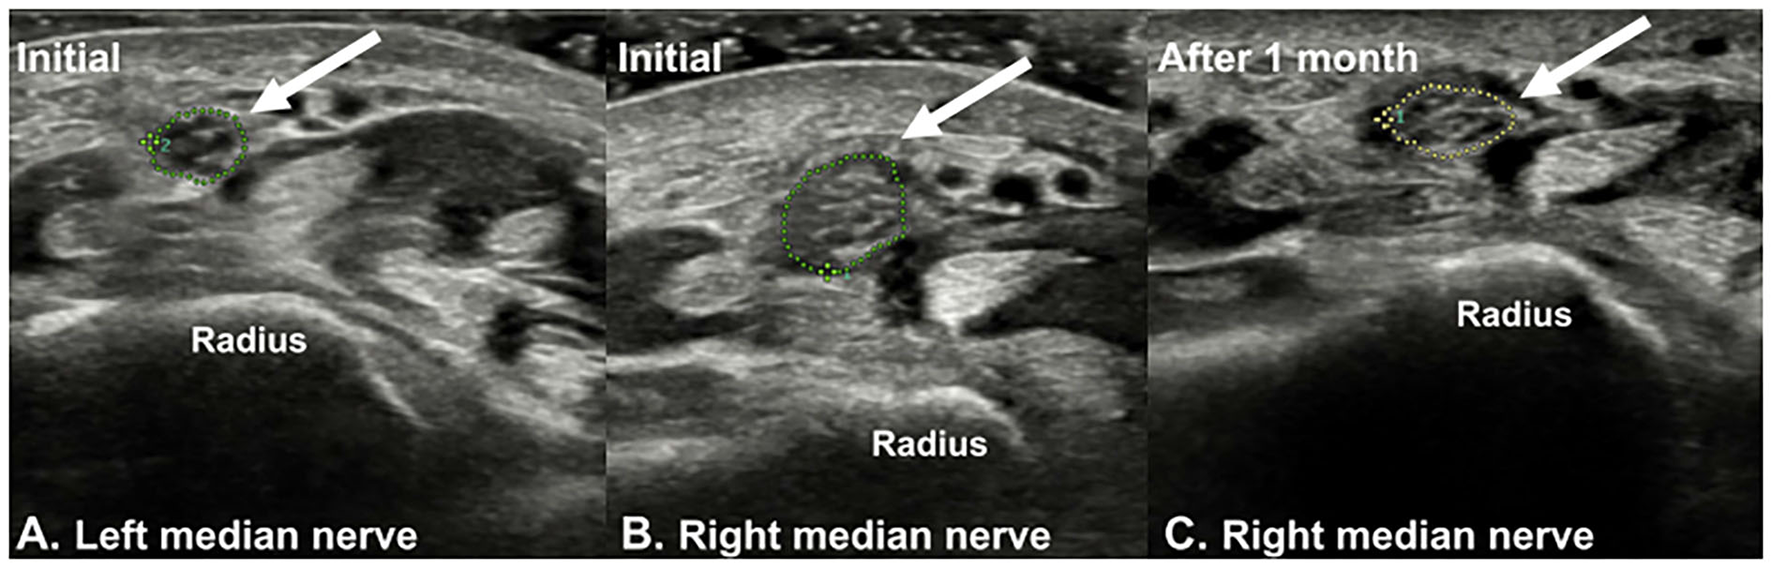

Plain radiographs showed no signs of fracture or other abnormalities. Ultrasound examination revealed a hypoechoic, swollen right median nerve, 4 cm proximal to the wrist crease. The cross-sectional area (CSA) of the right median nerve at the lesion site was 0.19 cm2, while that of the left median nerve was 0.09 cm2 (Figure 1). Magnetic resonance imaging (MRI) of the right forearm revealed edema in the surrounding fat tissue and a focal defect in the epineurium of the right median nerve, at the distal radius level (Figure 2).

Figure 1. Ultrasound imaging of (A) left median nerve and (B) right median nerve (arrow). The sonographic findings showed a hypoechoic swelling of the right median nerve at the distal forearm level (4 cm above the distal wrist crease). At this level, the cross-sectional area (CSA) of the right median nerve was 0.19 cm2, and that of the left side was 0.09 cm2. (C) At the 1-month follow-up, the CSA of the right median nerve was 0.12 cm2.

At the 1-month follow-up, the patient showed more than 80% improvement in the symptoms, and follow-up sensory NCS revealed improvement in the onset latency and amplitude of the median nerve (Table 1). On sonographic examination, the CSA of the right median nerve was 0.12 cm2, indicating improvement compared to the initial presentation (Figure 1). Further examinations could not be performed as the patient was lost to follow-up.